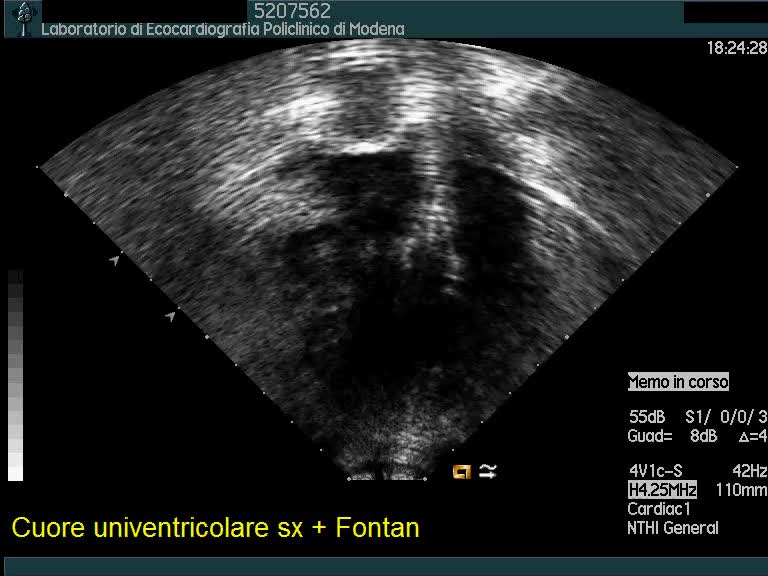

Cuore univentricolare

Autore:

Andrea Barbieri